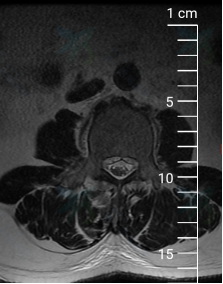

入院后给予逐级止痛治疗,但症状无明显缓解;为更加详细明确病因及病变位置,拟行腰椎MRI、左髋关节MRI及全身骨扫描等相关检查,但患者因剧烈疼痛无法平躺配合,为解决这一难题,遂邀请我院麻醉科会诊,在麻醉科谭敬老师、袁伟老师、宋珂珂老师的积极努力下,成功完成硬膜外麻醉并置管,患者疼痛症状明显缓解,使得检查顺利进行,结果显示:MRI检查示腰2/3椎体信号异常,再结合抽血检验示结核杆菌T细胞检测阳性这一指标,遂考虑病变部位可能为腰2/3结核感染可能。为进一步明确病变责任部位,于局麻下为该患者行腰3神经根封闭术,封闭后病人症状明显缓解,证实了先前诊断。杨益民副主任医师与患者及家属充分沟通后,决定采用微创椎间孔镜手术方式给予患者行结核病灶清除、神经根探查松解术,手术过程顺利,术后病人症状完全缓解,病人及家属对我院诊疗水平表示十分满意。

腰椎MRI示:腰2、3椎体信号异常,椎管内异常信号影